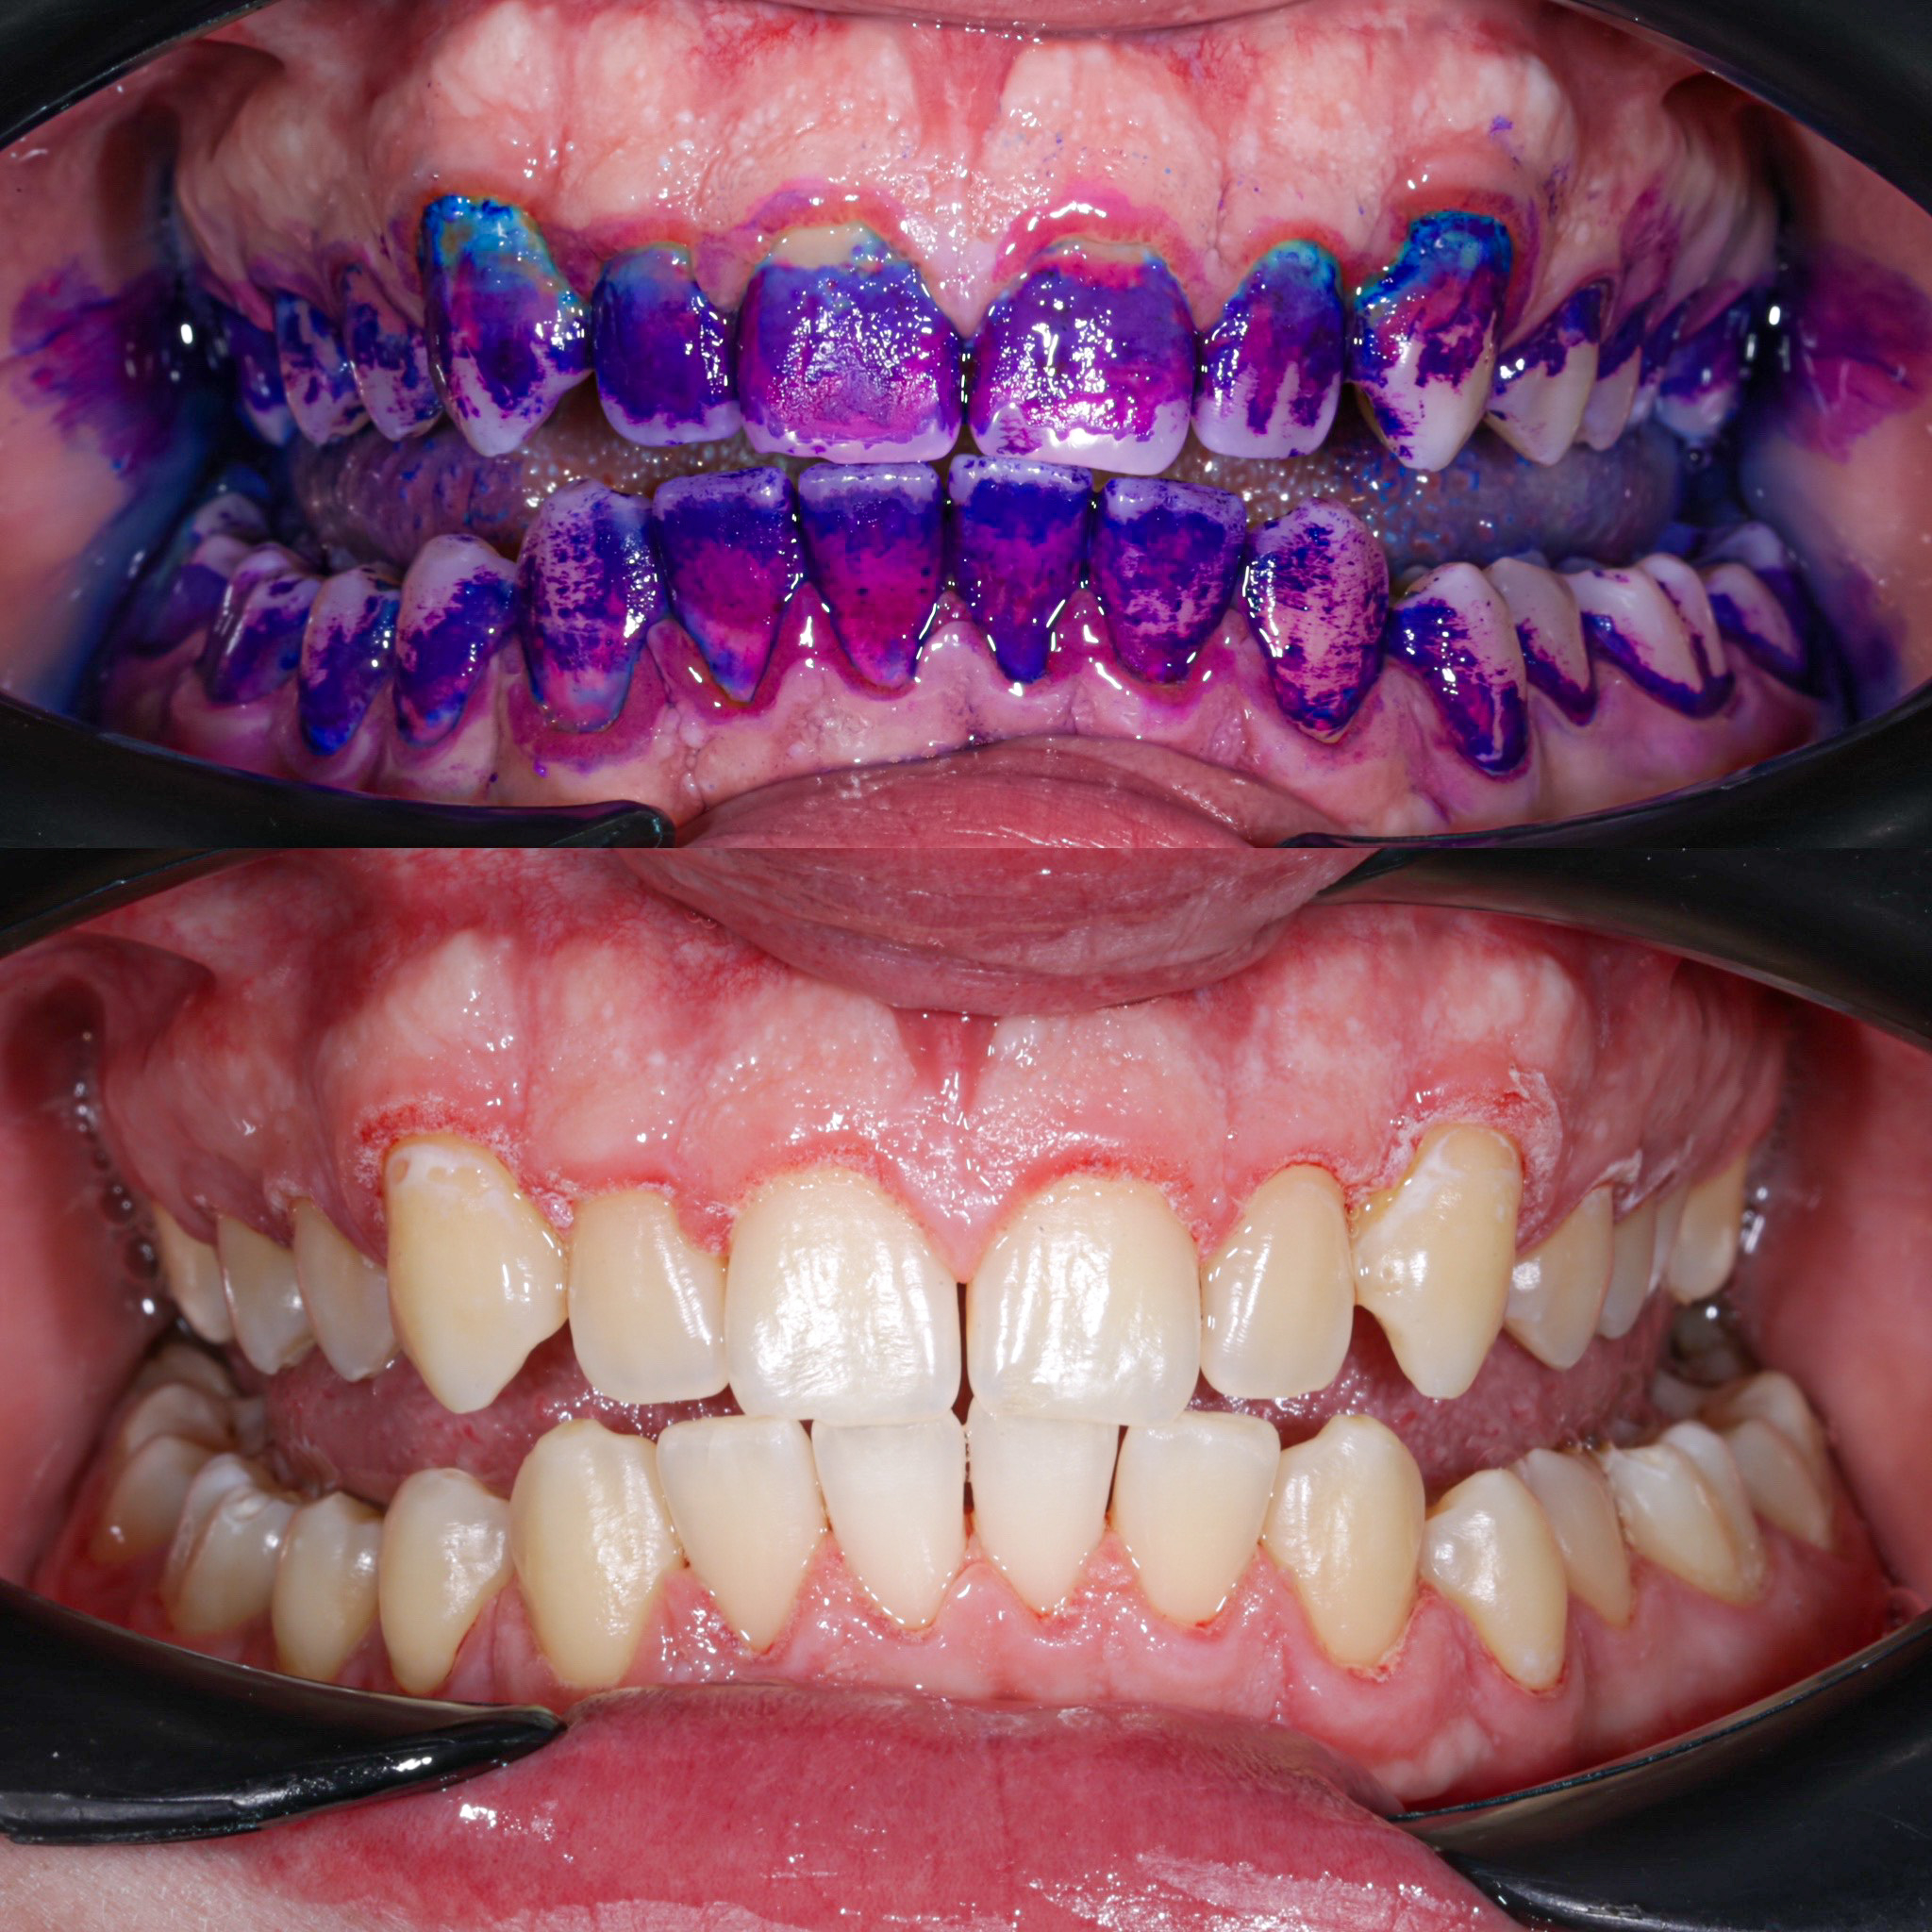

Повітряно-абразивна чистка зубів (Air Flow)

Завдяки піскоструменевому апарату з технологією Air Flow, який використовуючи тиск повітря та води, подає на зубну емаль спеціальний абразивний склад, зуби можна очистити не лише від м’якого нальоту, а й від пігменту. Для видалення нальоту, в Космічній стоматології Драганчука ми використовуємо KaVo prophy pearls supragingival calcium carbonateneutral.

• Зняття нальоту гігієнічними перлинами KaVo PROPHY pearls SUPRAGINGIVAL CALCIUM CARBONATE в індивідуальних пакуваннях із ароматом на вибір: персик, апельсин, м'ята, чорна смородина та нейтральний смак.

• Полірування швейцарською пастою Proxyt Ivoclar Vivadent для блиску та природної білизни.

Чистка зубів щіточками та пастами

Фінальний етап професійної гігієни - полірування спеціальними щіточками та пастою, щоб усунути мікротріщини та шорохуватості, що виникли після чистки та видалити залишки нальоту, що могли в них залишитись. Це дозволяє суттєво уповільнити формування нових відкладень.

Полірування зубної емалі гумками

Кінцеве полірування поверхні зубів проводиться із застосуванням різних насадок, зокрема спеціальних гумок, що надає зубам ідеальної гладкості та блиску. Спеціальні гумові насадки відмінно справляться з наданням естетичної довершеності твоїй посмішці.